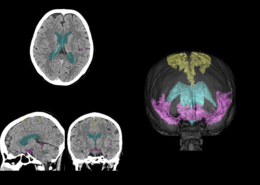

今回、富士フイルムと名古屋市立大学は、富士フイルムの「SYNAPSE Creative Space」を用いて、頭部CT画像上でDESHに関係する脳脊髄液腔の各領域(高位円蓋部・正中のくも膜下腔、シルビウス裂・脳底槽、脳室)を抽出するAI技術を開発した。昨年MRI向けに開発した技術を、MRI検査と比べて検査時間が短いことなどから医療現場で広く普及しているCT検査向けに発展させたものである。本技術は、頭部CT画像上でDESHに関係する各領域のアノテーション作業を効率的に行い作成したデータをAIに学習させて開発したもので、CT画像上で脳脊髄液腔の各領域を抽出できる。さらに、領域ごとの体積や領域間の体積比を算出することにより、脳萎縮とハキム病の判別に重要な画像所見であるDESHの判定に大きく寄与し、ハキム病の診断精度向上につながることが期待できる。

CT画像上で本技術を用いて脳脊髄液腔の各領域を抽出した例